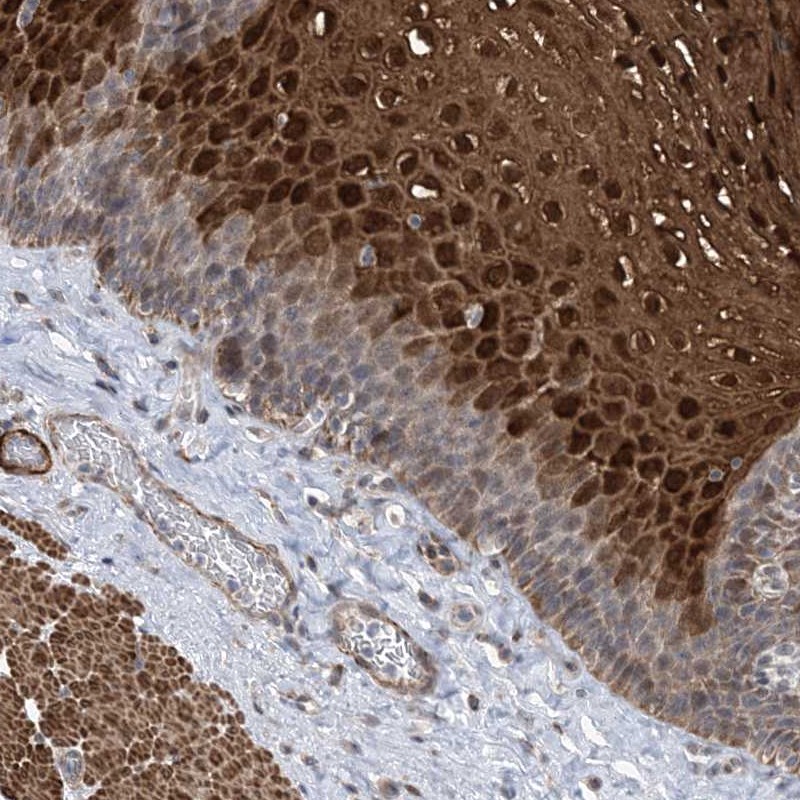

Immunohistochemical staining of human esophagus shows strong nuclear and cytoplasmic positivity in superficial cells of squamous epithelia.